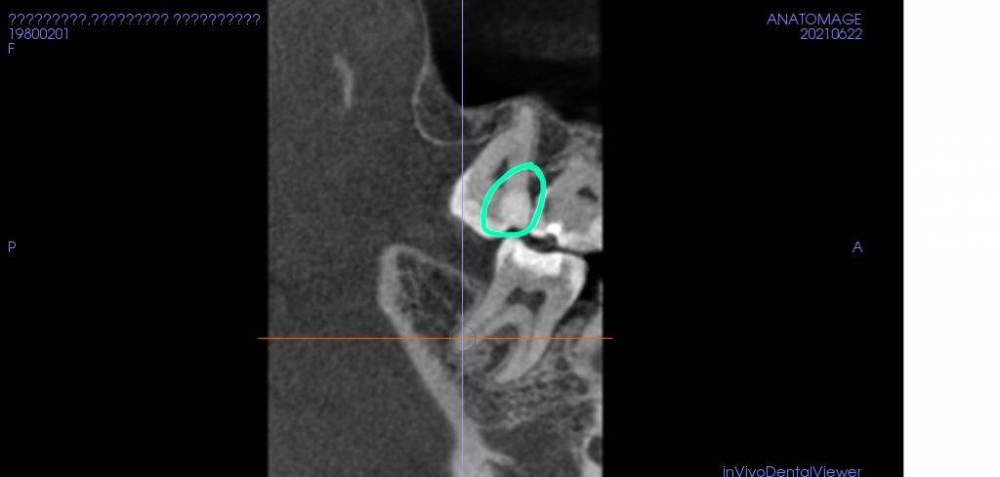

Jule Hune Опубликовано 25 июня, 2021 Поделиться Опубликовано 25 июня, 2021 Очень нужно ваше мнение специалиста! Помогите, пожалуйста, разобраться! Вопросов у меня несколько, начну с первоочередного. Больше недели назад лечили зуб, снимок прикладываю, область новой пломбы обведена зеленым. Как сказала врач лечили средний кариес. До вмешательства ничего не беспокоило. Зуб болит, поднывает спустя неделю. Спустя ровно неделю после пломбировки врач проверил током, зуб показывает высокие показатели (от 30 возникает чувствительность), то есть диагностируется пульпит. До вмешательства вообще ничего не беспокоило! Подскажите, пожалуйста, если зуб какой-то время лечился без воды (вода в бормашине заканчивалась) могло это вызвать воспаление пульпы/нерва? Ссылка на комментарий

dentikl Опубликовано 25 июня, 2021 Поделиться Опубликовано 25 июня, 2021 Там полость почти в проекции пульповой камеры.Не мог этот зуб не беспокоить до вмешательства.Идите к врачу. Ссылка на комментарий

Jule Hune Опубликовано 25 июня, 2021 Автор Поделиться Опубликовано 25 июня, 2021 Спасибо за ответ! Мог или не мог - это точно понятно! НЕ БЕСПОКОИЛ до. ? Что значит "идти к врачу". Я как раз была. Вначале врач вылечила эту область, поставила новую пломбу, через неделю я у нее была, проверяли током зуб и соседний на пульпит, дули воздух, стучали, сделали прицельный снимок, затем снимок КТ этой области. Что еще нужно сделать? (Здесь интересует как раз альтернативное мнение профессионалов). Спасибо за ответы! Ссылка на комментарий